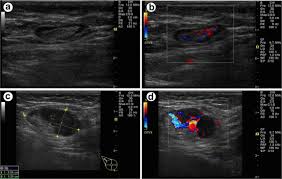

When is breast ultrasound used? Breast ultrasound breast ultrasound uses sound waves to make a computer picture of the inside of the breast. Many calcifications seen on mammography cannot be seen on ultrasound. Ultrasound imaging allows better evaluation of the status of the axillary lymph nodes in patients with ibc, an important step in determining extent of disease prior to initiation of chemotherapy. The data presented in this article reviews the medical images of breast cancer using ultrasound scan.

However, a dark spot on your ultrasound doesn't mean that you. Characteristics of malignant breast cancer on ultrasound are speculation, deeper (taller) than wide, microlobulations, thick hyperechoic halo, angular margins, markedly hypoechoic nodule, posterior acoustic shadowing, branching pattern, punctate calcifications, duct extension and heterogeneous echotexture. Signs of inflammatory breast cancer. Mammography is the least sensitive imaging. Breast ultrasound breast ultrasound uses sound waves to make a computer picture of the inside of the breast.

Other ultrasound findings that suggest breast cancer include: You can get dressed straight after the ultrasound. During a breast exam, your doctor looks for visual changes and uses their fingers to feel. That indicates that the lesion likely contains a variety of elements, which may or may not indicate breast cancer. You might not need any further tests if everything looks normal.

Has skin that looks dimpled or ridged like an orange. Density is a term used to describe breast tissue that has many glands close together. You might not need any further tests if everything looks normal. Other ultrasound findings that suggest breast cancer include: Tubular carcinoma of the breast is a subtype of invasive ductal carcinoma (idc). It is the most common cause of cancer death in women. in 2005 alone, 519 000 deaths were recorded due to breast cancer. this means that one in every 100 deaths worldwide and almost one in every 15 cancer deaths were due to breast cancer. Breast ultrasound dataset is categorized into three classes: Ultrasound is one of the tools used in breast imaging, but it does not replace annual mammography. While it may look like a fuzzy, spotty television screen with different shades of grey to a patient, the ultrasound technician and the radiologist use these images to diagnose masses and tumors. The peak age at presentation may be comparatively younger than with other types of breast cancer 7. Signs of inflammatory breast cancer. Cysts, tumors, and growths will appear as dark areas on the scan. You can get dressed straight after the ultrasound.